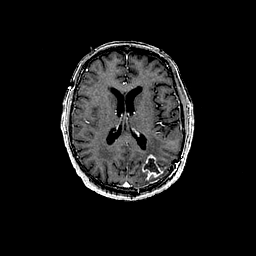

Glioma overlay -- Slice #67

[Home][Help][Clinical] Slice 67